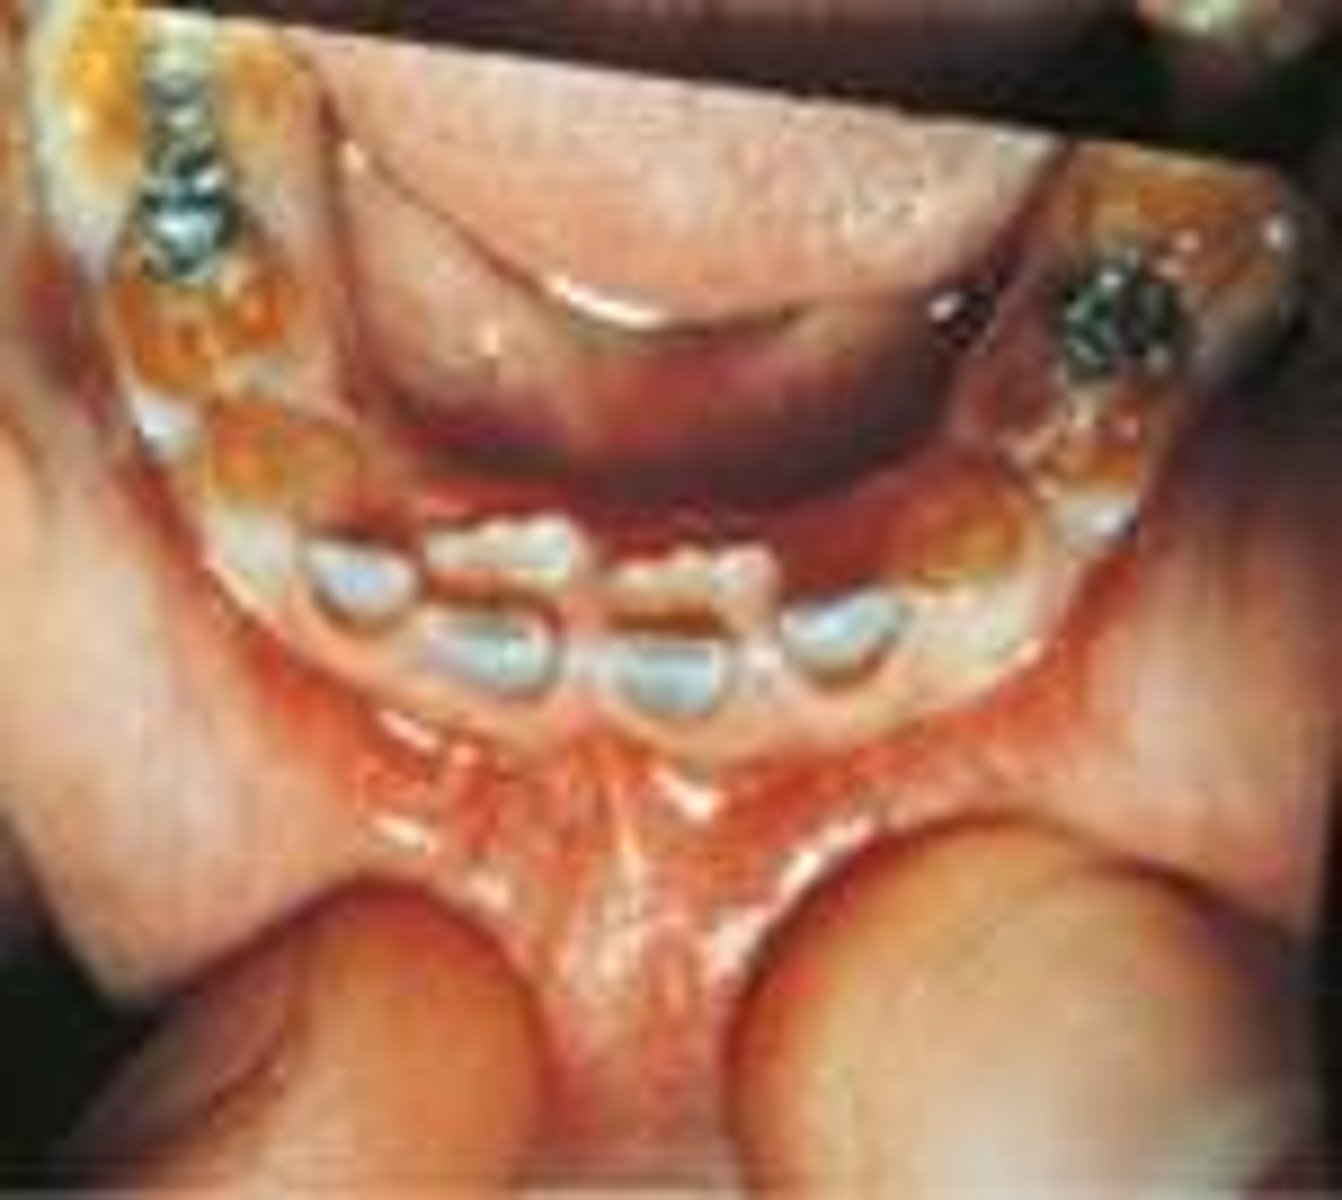

Gingival and periodontal disease has been reported in _______ of affected individuals with down syndrome

90%